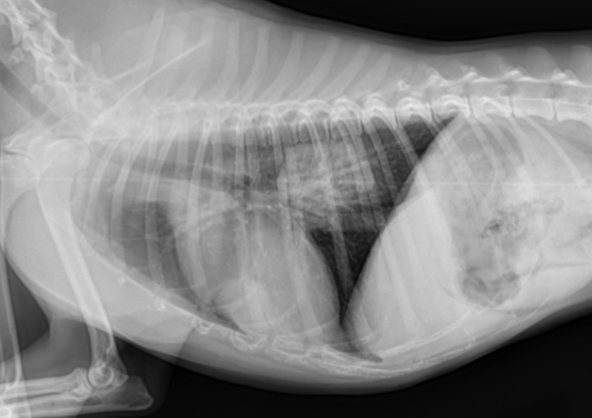

how is megaesophagus diagnosed?

-cervical and thoracic radiographs +/- oral contrast

how are hiatal hernias diagnosed?

may manifest intermittently

-thoracic radiographs: caudodorsal, gas-filled intrathoracic soft-tissue opacity

-contrast videofluoroscopy swallow study (normal does not rule out a hiatal hernia)